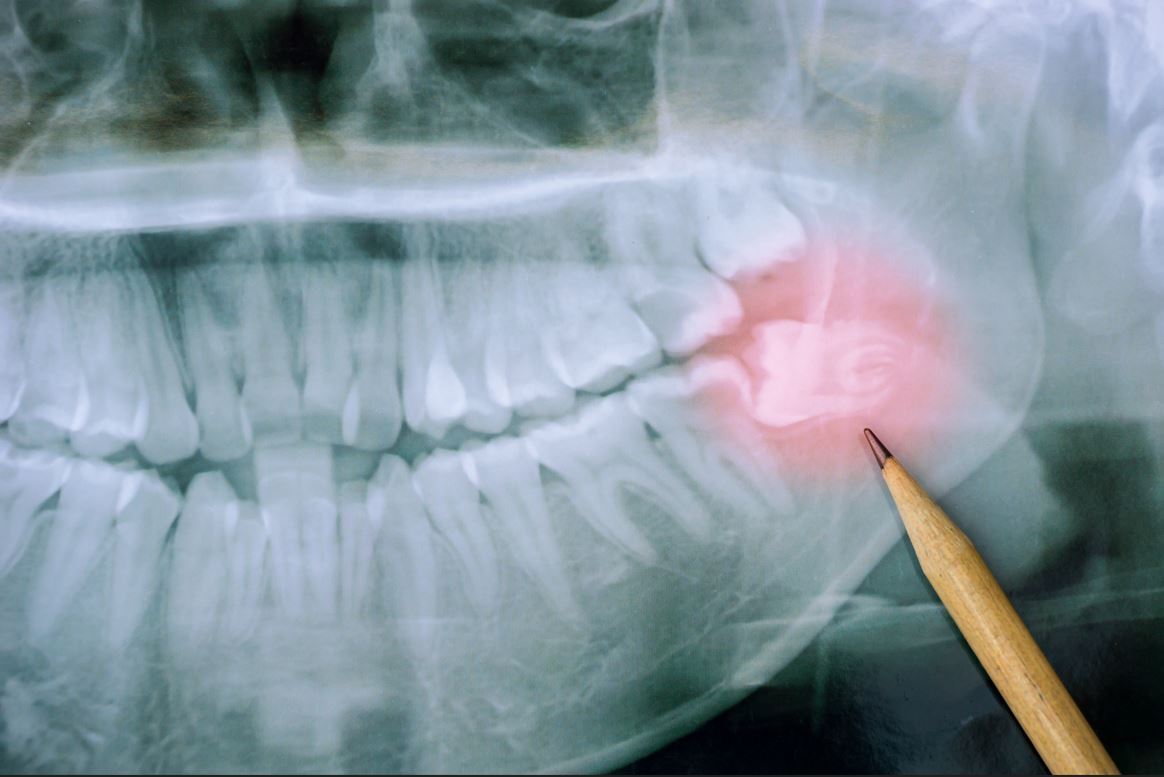

Kieferzysten

Kieferzysten sind mit Flüssigkeit gefüllte Hohlräume im Kieferknochen oder im Weichgewebe des Mundraums. Sie sind in der Regel gutartig, sollten aber wegen ihrer Wachstumstendenz entfernt werden. Der durch die Zystenentfernung (Zystektomie)entstandene Hohlraum füllt sich in der Regel durch natürliche Heilungsprozesse. Bei großen Zysten kann ein Auffüllen mit Knochenersatzmaterial sinnvoll sein. Unter Umständen reicht es aus, die Zyste lediglich zu eröffnen (Zystostomie), sodass die enthaltene Flüssigkeit abfließt. Der Druck im Inneren der Zyste nimmt ab, das Wachstum wird gestoppt.

Insbesondere die Entfernung der Weisheitszähne ist für viele Jugendliche und auch für Erwachsene eine unangenehme Vorstellung. PD Dr. Dr. Safi verwendet minimalinvasive Verfahren um schwierige Zahnentfernung so bequem und komfortabel wie möglich zu gestalten. Eine Entfernung wird häufig notwendig, wenn die Weisheitszähne infolge von Platzmangel zu Komplikationen wie Zahnverschiebungen, Zysten, Abszessen und anderen Problemen führen können. Auch weiterführende Beschwerden wie Kopfschmerz, Schwindel oder Nackensteifigkeit können von den Weisheitszähnen verursacht werden.